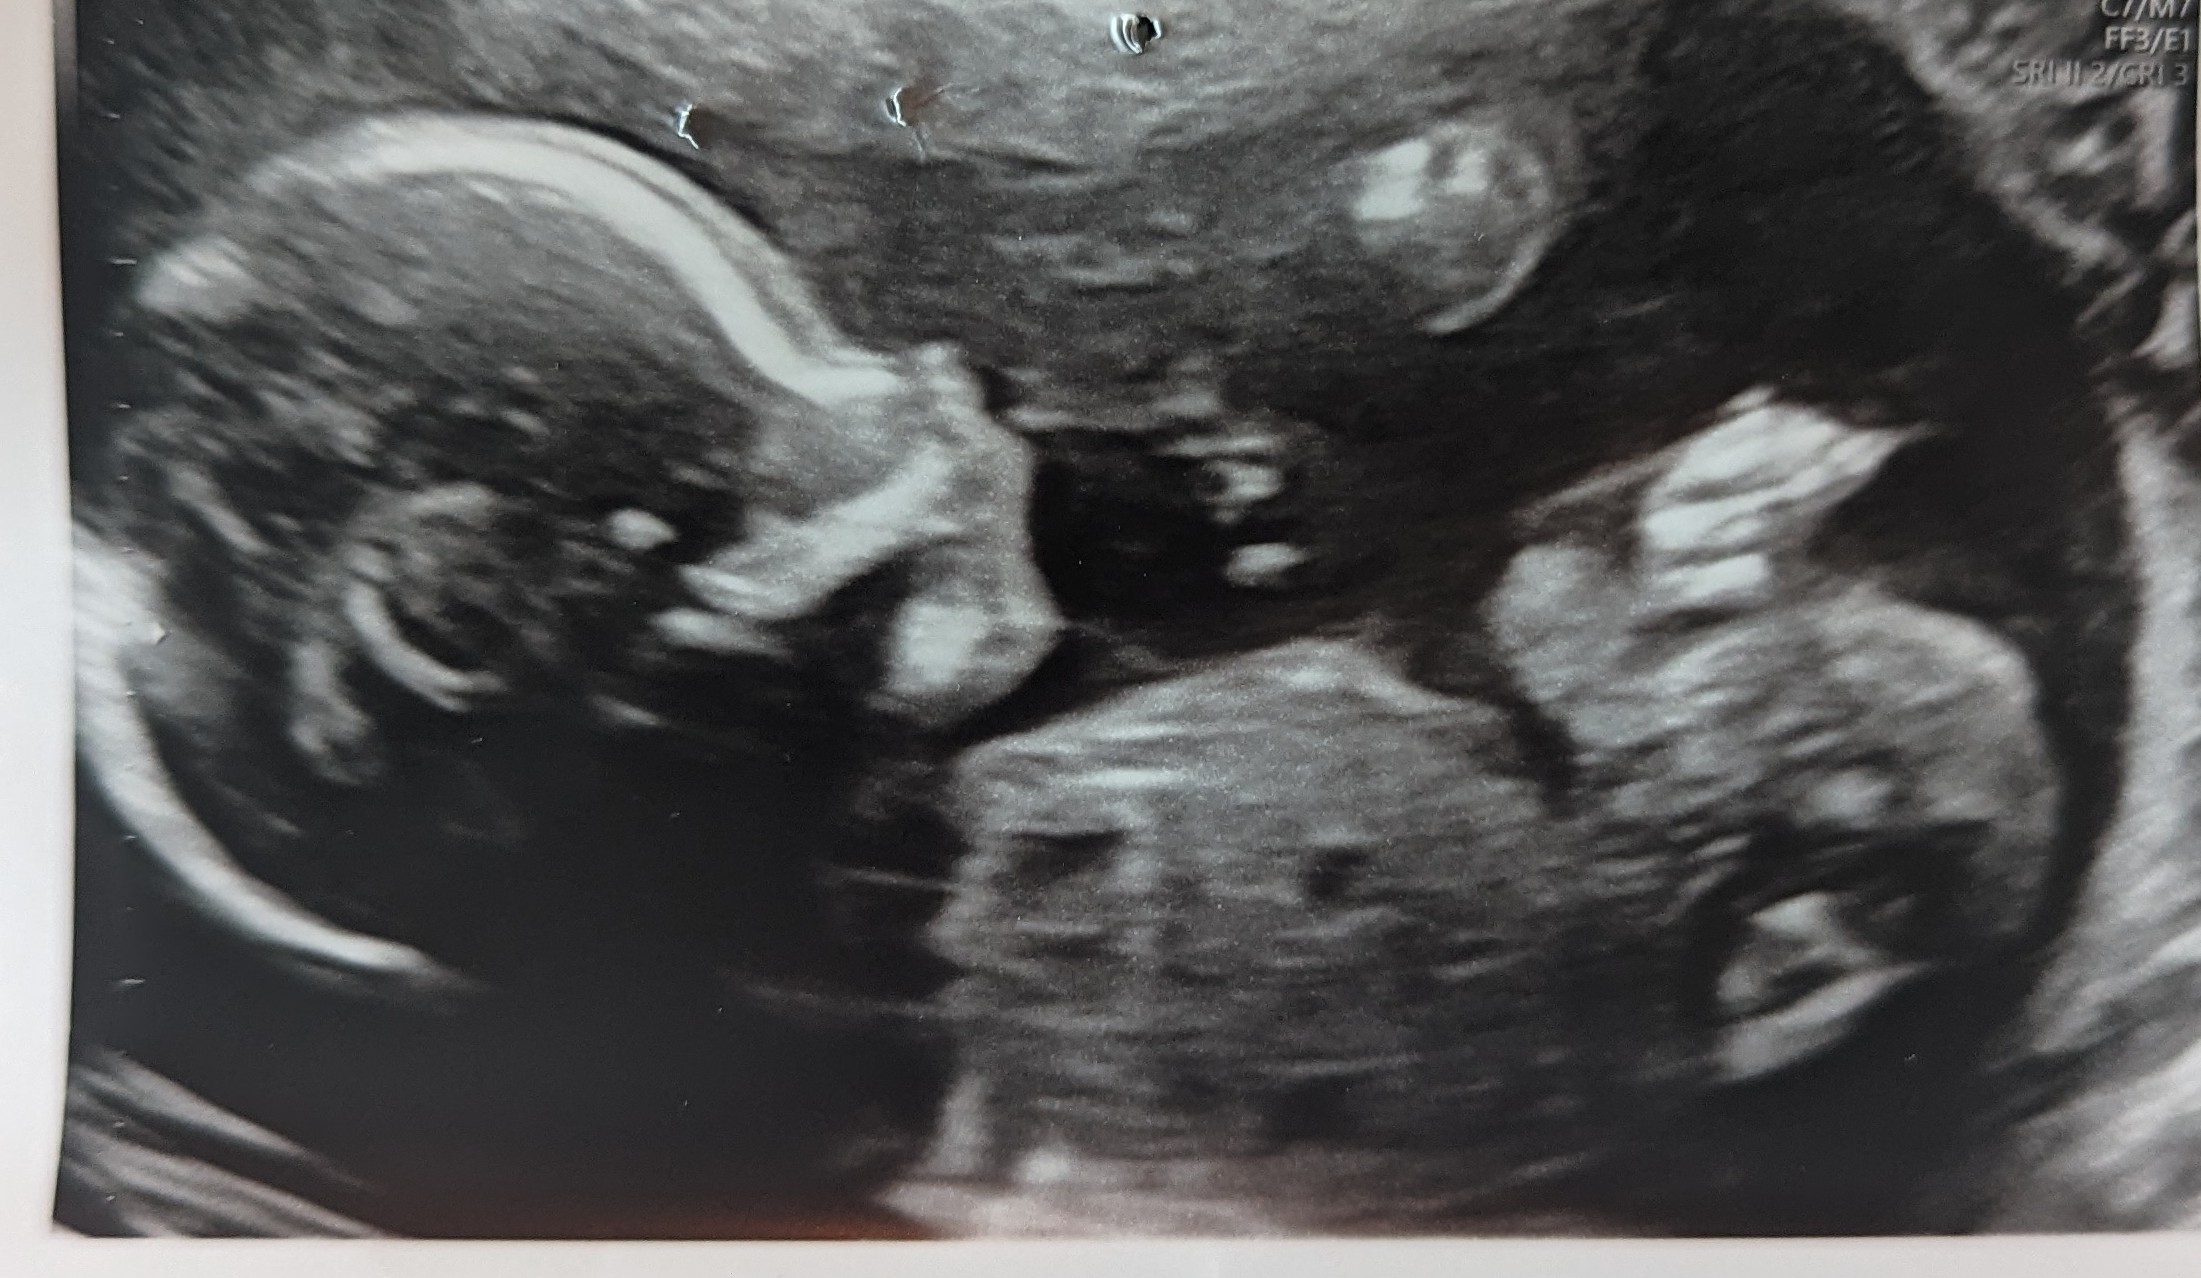

- ordinær ultralyd 20+0

- få vite om barnet er friskt

- få vite kjønn